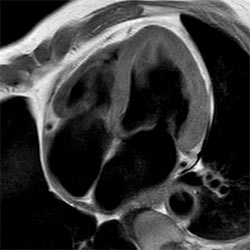

Geri ödemelerin azaldığı ve kronik şartların MR prosedürlerinin artmasına ve daha uzun bekleme sürelerine yol açtığı bir toplumda, radyoloji departmanları üzerindeki baskı gittikçe artmaktadır. Bugün, daha fazla hızlanma için görüntü kalitesinden ödün vermek veya daha az görüntüleme yapmak durumunda kalınmaktadır. Bu nedenle, artan verimlilik talebini karşılamak için hızlanmada bir teknolojik gelişme daha gereklidir. Philisp, hız konusunda (SENSE gibi) uzun süredir devam eden liderlik konumumuzu güçlendirerek üretkenlikte yepyeni bir atılım olan Compressed SENSE'i getiriyor.

Compressed SENSE'in temel ilkeleri ve verimlilikteki yaklaşımsal değişikliğini keşfetmek, Compressed SENSE'in görüntü kalitesi odaklı nasıl tasarlandığı, ve klinik MR görüntülemede verimliliğe nasıl yarar sağladığı görmek için daha fazla bilgi edinin.

MR görüntülemeyi birçok farklı kontrast tiplerinde ve sekanaslarda yapabilen, 2D ve 3D görüntülemeleri hızlandıran Compressed SENSE hakkında daha detaylı bilgilenmek için Kantonsspital Winterthur'ın (İsviçre) deneyimlerinden faydalanın.